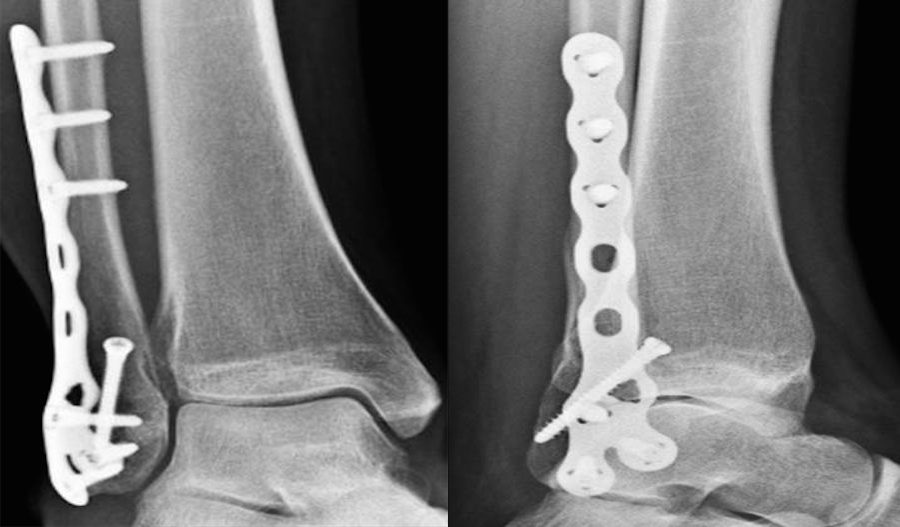

Locking Plates: What Have We Learned? Although traditional plate designs date back decades, these authors discuss the emergence and potential of locking compression plates, polyaxial locking plates, and minimally invasive plate osteosynthesis. HYPERLINK "https://s3.amazonaws.com/HMP/hmp_ln/imported/pt0915locking1ab.png" \t "_blank" The popularization of traditional plate and screw constructs dates back to the late 19th century as well as the efforts of the Belgian surgeon Robert Danis, MD.1,2 This discovery along with Danis’ publication of Over the past several decades, as surgeons have gained a better understanding of the utility of plate and screw constructs, the application of the devices has evolved. In addition to incorporating these devices into the surgical repair of fractures, surgeons may utilize them for joint arthrodesis and other reconstructive osseous surgeries. One advance with these modalities has been the advent and evolution of the locking plate construct, which has several applications within foot and ankle surgery. Reviewing The Different Kinds Of Plate Fixation HYPERLINK "https://s3.amazonaws.com/HMP/hmp_ln/imported/pt0915locking1cd.png" \t "_blank" Neutralization plates function as load-sharing apparatuses that shield lag screws from the torsional forces the surgeon encounters during range of motion.4 Buttress plates and anti-glide plates are load-bearing devices that can support a section or segment of bone, which are frequently areas of impaction associated with significant comminution of the cortex, thus leaving a compromised diaphyseal construct and/or voids within the cancellous bone. By fixing the plate proximally and distally to stable areas of bone, the surgeon can prevent the segments from re-approximating during axial loading.5 There are two kinds of compression plates: static compression plates and dynamic compression plates. With the static compression plate, the compression yielded at the fracture interface is secondary to the tension one applies to the implant. This technique is beneficial for those transverse or short oblique fractures when insertion of a lag screw is not attainable. In order to achieve compression, drill the initial screws eccentrically through oval holes in the plate away from the fracture site. As the screw heads contact the plate and sit centrally in the oval holes, the fragments compress together. The dynamic compression plate adheres to the tension band principle. This refers to the application of a plate on the tension (convex) side, preventing gapping that normally would occur and converting the distracting forces into compression forces. The placement of a plate to bone serves as both an expediter and a temporary inhibitor of osseous repair.5 HYPERLINK "https://s3.amazonaws.com/HMP/hmp_ln/imported/pt0915locking2abc.png" \t "_blank" Certain plate designs have addressed the effects of reduced blood flow that can occur underneath a plate due to reduced bone density. This plate-associated osteoporosis has a detrimental effect on the mechanical properties of healing bone. Limited contact dynamic compression plates were designed with recesses or undercuts in the plate to reduce contact between the plate and the bone, therefore reducing the risk of plate-associated osteoporosis. Recognizing The Potential Benefits Of Locking Compression Plates There have been efforts to improve the weakest part of the construct (the screw-bone interface) by increasing the contact area between the screw and the bone with the placement of screws in polymethyl methacrylate (PMMA) or by creating a single-beam construct. This is the principle behind locking plates with the creation of a construct to address the lack of motion between the components of the beam (i.e., the plate, screw and bone).6 HYPERLINK "https://s3.amazonaws.com/HMP/hmp_ln/imported/pt0915locking2def.png" \t "_blank" The locking compression plate arose from the desire to increase stability, which at the time was limited by the torque generated during screw purchase into the plate-bone interface. Cancellous, osteoporotic or pathologic bone and comminution limit the amount of torque that one can generate to enhance stability.7 This led to the development of the locking compression plate, which has the ability to preserve the blood supply to bone by reducing periosteal stripping. The traditional plating techniques provided stability by compressing the plate to the bone surface with the screws achieving bicortical purchase as the second point of fixation. However, locking compression plate technology features unicortical locking screws that can be an “internal fixator” that can act as a bridge over compromised bone.8 However, in areas or regions where high torsional and axial loads are expected, one should utilize bicortical locking screws. With locking plates, the sum of all the interfaces between the screws and bone equals the strength of fixation as opposed to the unlocked plates’ single screw pullout strength.7 One of the benefits of locking plates is their ability to be “bridge plates,” whereby they provide excellent axial and angular stability, preserve fragmentary blood supply, and reduce the risk of loss of reduction. Indeed, surgeons do not have to contour these plates anatomically to the bone, and the plates have the potential benefit of providing superior fixation in osteoporotic bone. Indications for the use of locking plates include diaphyseal/metaphyseal fractures in osteoporotic bone, multifragmentary diaphyseal/metaphyseal fractures, osteotomies in at-risk patients (poor bone stock, revisions, etc.), articular fractures, segmental fractures with multiple patterns, and any combination of the above.9 HYPERLINK "https://s3.amazonaws.com/HMP/hmp_ln/imported/pt0915locking3ab.png" \t "_blank" In their guidelines for using the locking compression plate, Gautier and Sommer emphasize the importance of the reduction technique, minimally invasive plate insertion and fixation to keep bone viability undisturbed.9 Pertinent Insights On Minimally Invasive Plate Osteosynthesis HYPERLINK "https://s3.amazonaws.com/HMP/hmp_ln/imported/pt0915locking3cd.png" \t "_blank" Minimally invasive plate osteosynthesis maintains bone vascularization with minimal periosteal stripping, thus improving bony consolidation and decreasing operative time, complications and infection rates. The application of a locking plate using the minimally invasive plate osteosynthesis technique generally consists of making small incisions proximal and/or distal to the fracture site, percutaneous reduction and subsequent extraperiosteal placement of the plate with any radiolucent percutaneous guide. Can Polyaxial Locking Plates Have An Impact? A recent study by Cullen and colleagues looked at a biomechanical comparison of polyaxial and uniaxial locking plate fixation in extra-articular proximal tibia metaphyseal fractures.10 A Closer Look At Potential Contraindications And Complications Currently, there are no absolute contraindications for locking plates. However, there are instances when applying them may be unnecessary. A good example would be in a case with a simple fracture pattern in a healthy patient with good quality bone. Another case would be a fracture pattern where the surgeon is trying to achieve compression through the plate itself without the addition of a lag screw. Also, if a patient has an oligotrophic non-union and the cause of the delayed healing is not related to an insufficient amount of stability, one should not employ locking plates. Another matter to keep in mind is the increased cost of a locking plate-screw construct versus traditional plate-screw designs, which in some cases can be substantial. As always, consider the possibility of a metal allergy or intolerance. HYPERLINK "https://s3.amazonaws.com/HMP/hmp_ln/imported/pt0915locking4def.png" \t "_blank" One of the more common complications with locking plates is creating an environment of too much stability, thus becoming “non-union generators.”11 Final Thoughts As we previously discussed, it is important to tailor the fixation of choice to the fracture pattern and location, the underlying bone quality and the overall needs of the patient. We still need to see more clinical data on locking plate technology in order to determine specific clinical scenarios in which the additional cost may be justified. Dr. Fidler is a Fellow at the Orthopedic Foot and Ankle Center in Westerville, Ohio. Dr. Prissel is a Fellow at the Orthopedic Foot and Ankle Center in Westerville, Ohio. Dr. Hyer is the Fellowship Director of the Advanced Foot & Ankle Surgical Fellowship in Westerville, Ohio. He is a Fellow and a member of the Board of Directors for the American College of Foot and Ankle Surgeons. References 1 2 3 4 5 6 7 8 9 10 11